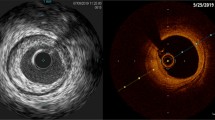

Adlam et al. performed elective angiography (n = 42) with OCT (n = 16) and IVUS (n = 21) assessment of patent SVG in asymptomatic patients 3 years after surgery [3•]. As such, this was SVG imaging outside of the acute coronary syndrome (ACS) setting. Fifty-five percent of SVGs were occluded [3•]. Typical findings in patent SVG were of the double-layered appearance of the vessel wall due to neointima formation with neointimal thickness varying both between patients and within different segments of the grafts (Fig. 1) [3•]. The patent grafts imaged had no significant stenotic disease—the implication was felt to be that there is a high rate of SVG failure by 3 years out from CABG, but that grafts which continued to be patent by that time seemed to have little stenotic disease or were “survivors” of sorts. The authors found that OCT, but not IVUS, was best capable of identifying features of atherosclerosis, including circumferential fibrous neointima, thin-cap fibroatheroma (Fig. 2), and adherent thrombus [3•]. OCT, but not IVUS, demonstrated findings consistent with thin-cap fibroatheroma (TCFA) in 6 of 16 SVGs and luminal adherent thrombus in 4 of 16 SVGs. It was proposed that those features could indicate vein grafts vulnerable to future occlusion and that OCT could be useful in characterizing mechanisms of graft failure/graft pathology.

Neointima in example SVG shown angiographically and with OCT and IVUS. Example images by optical coherence tomography (OCT) (A–D) and intravascular ultrasound (IVUS) (E–H) from saphenous vein grafts (SVGs) shown angiographically (I–L) for the same 4 patients. Typical findings were of a double-layered appearance of the vein graft vessel wall due to neointima formation within the original vein graft wall. Neointimal thickness varied both between patients and within different segments and sectors of the grafts. [3•]